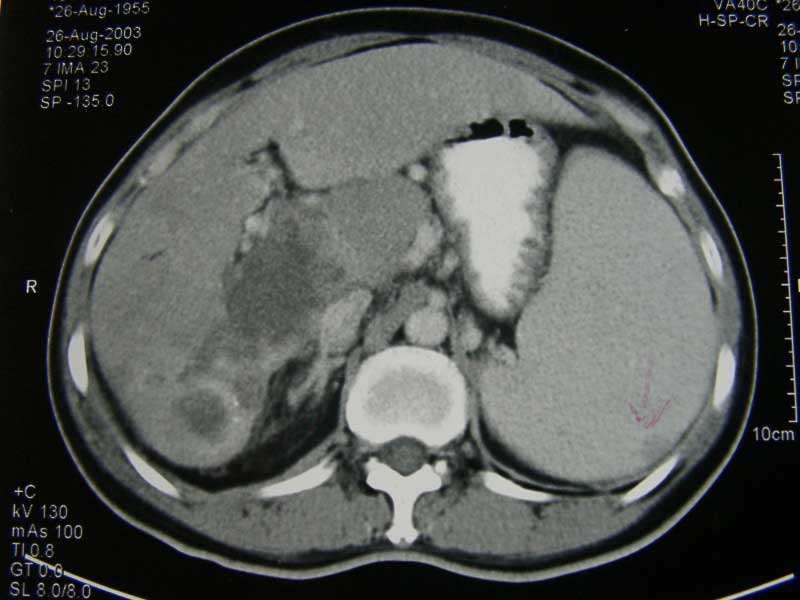

Seam (B984) a 49-year old female, was diagnosed with hepatocellular carcinoma in August 2003. CT abdomen on 26 Aug 2003 indicated:

- 8.7 x 6.6 x 10 cm mass in Segment 6 & 7 of liver

- Caudate lobe ruptured

- Peritoneal nodules

- Portal vein thrombosis

- Splenomegaly (swelling of the spleen)

- And probably splenic metastases.